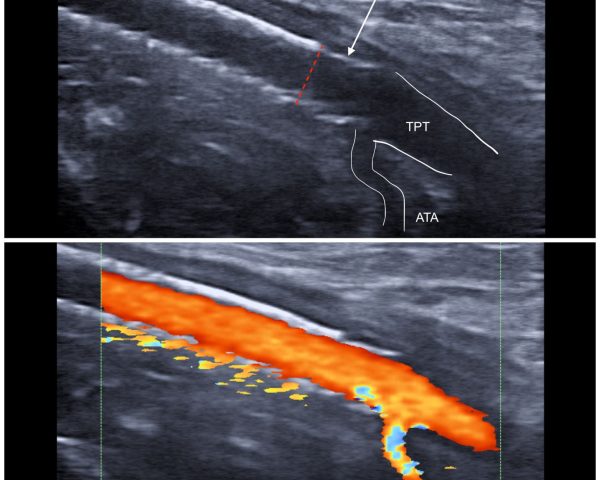

Seguimiento con eco-Doppler a 6 meses

En el seguimiento a 6 meses mediante eco-Doppler, se confirma la permeabilidad del segmento tratado, con flujo adecuado hacia las arterias tibiales. Desde el punto de vista clínico, el paciente: